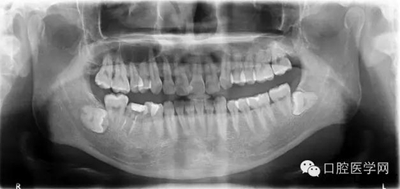

輔查:曲面斷層觀(guān)察齒c槽隔情況,為種植支抗植入熟悉解剖。

檢查:口內(nèi)恒牙列,上頜牙弓寬于下頜,右側(cè)第一磨牙第二磨牙正鎖合右下第一磨牙合面見(jiàn)大面積牙色充填物,牙面磨耗嚴(yán)重,咬合緊。